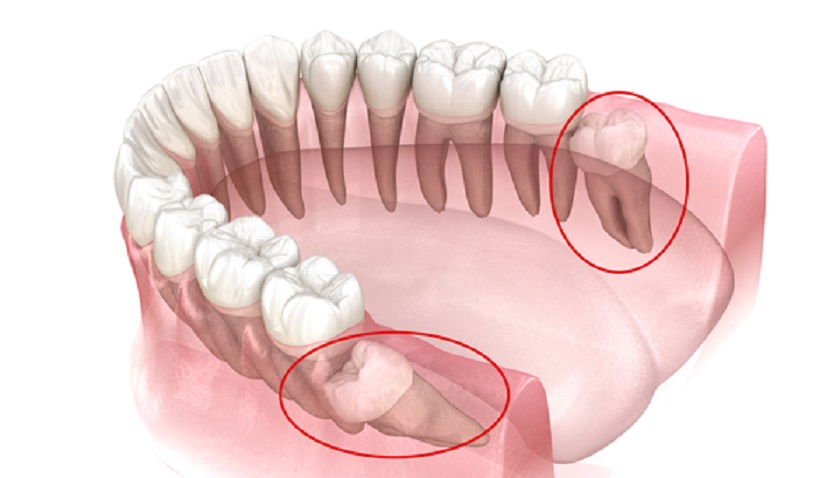

Răng mọc ngầm được phân chia thành các trường hợp cụ thể bao gồm răng khôn mọc ngầm và răng thường mọc ngầm. Biện pháp xử lý răng ngầm sẽ khác nhau trong từng trường hợp tùy theo vị trí mọc cũng như những tác động của răng ngầm đến sức khỏe răng miệng. Cụ thể như sau:

Nhổ răng là giải pháp nhanh chóng và hiệu quả trong trường hợp răng khôn mọc ngầm